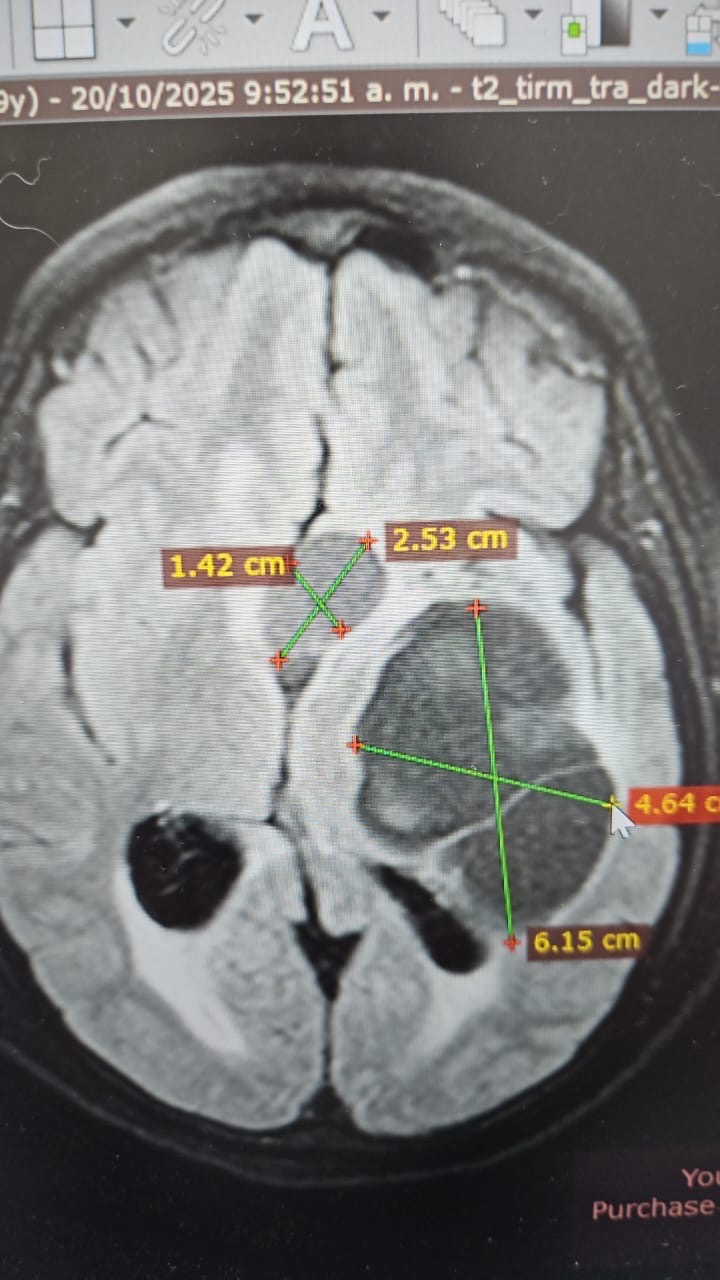

Hola, mi nombre es Yraida y estoy recaudando fondos para mi prima Ana, quien tiene varios quistes y dos tumores en el cerebro (adenoma hipofisario y craneofaringioma) y necesita una operación urgente.

Hello, my name is Yraida, and I am raising funds for my cousin Ana, who has several cysts and two brain tumors (a pituitary adenoma and a craniopharyngioma) and urgently needs surgery.